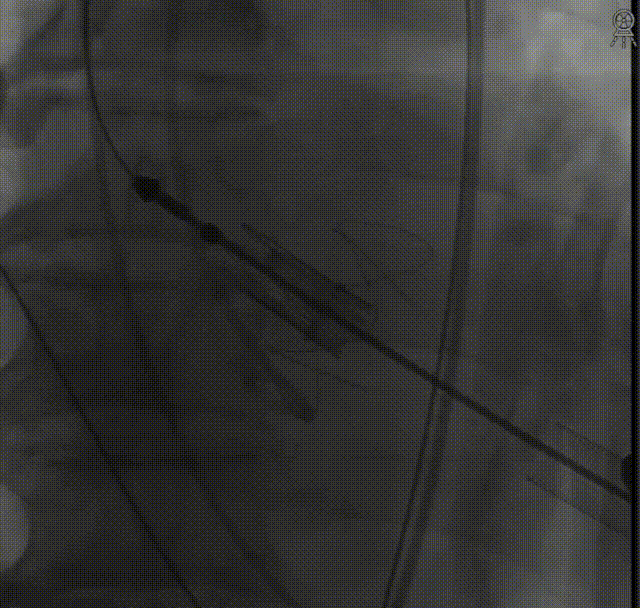

于右冠植入冠脉支架一枚,冠脉血流通畅:

定位件入窦后造影: